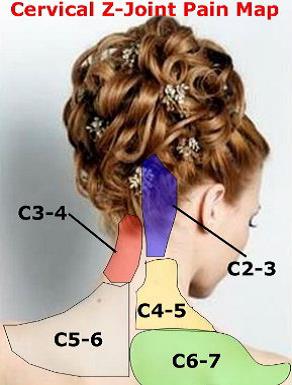

Il dolore da sindrome delle faccette articolari ha diverse caratteristiche a seconda della regione della colonna vertebrale danneggiata. Quando è affetta a parte più alta (cervicale) della colonna, il dolore si sente nella nuca ma può interessare anche le spalle e scendere lungo la schiena.

Spesso è accompagnato da cefalee, mal di testa.